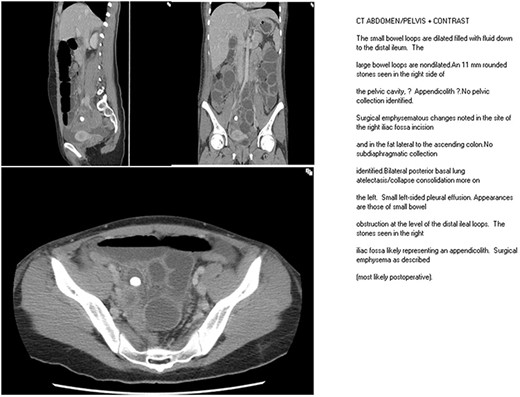

Unfortunately, from Day 2, post operatively the patient started developing symptoms of nausea, vomiting and moderate abdominal pain. On examination, she had mild abdominal distension with minimal tenderness in the lower abdomen with no signs of peritonitis. Blood tests did not display any significant changes. The abdominal radiograph showed dilated small bowel loops and an appendicolith in the right iliac fossa. A computerized tomography scan was performed and demonstrated dilated small bowel loops down to the distal ileum and a 11 mm appendicolith/stone in the right side of the pelvic cavity with no pelvic collection or other positive findings. The clinical diagnosis was that of an ileus, and she was treated conservatively with analgesia, nasogastric intubation and intravenous fluids. In the next 24 hours, her symptoms did not resolve, the abdominal distension progressively worsened with increasing lower abdominal pain and peritonism.